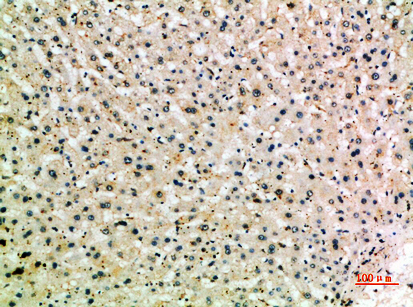

Anti-PAK2 AntibodyA97767

ApplicationsELISA, ImmunoHistoChemistry

ReactivityHuman, Mouse, Rat